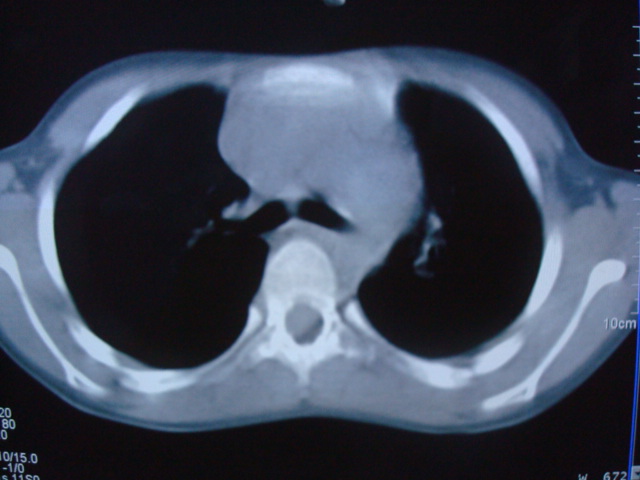

标题: PED0869:男,10岁,肺内多发结节+胸水

男,10岁,左胸痛,发热轻,血象高。后到省级权威医院治疗,病情明显好转,结果几天后公布。老机器,图像质量差,见谅。